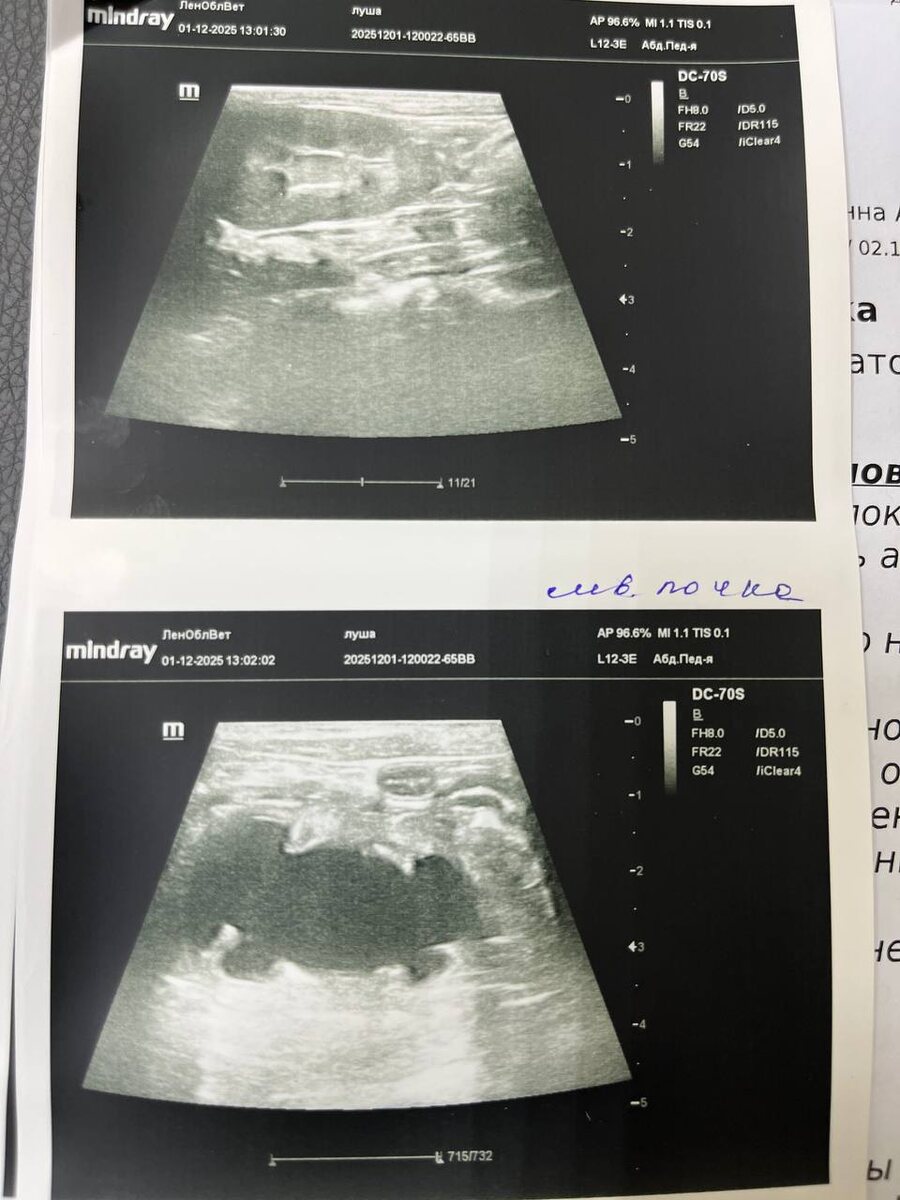

Результат УЗИ и рекомендации